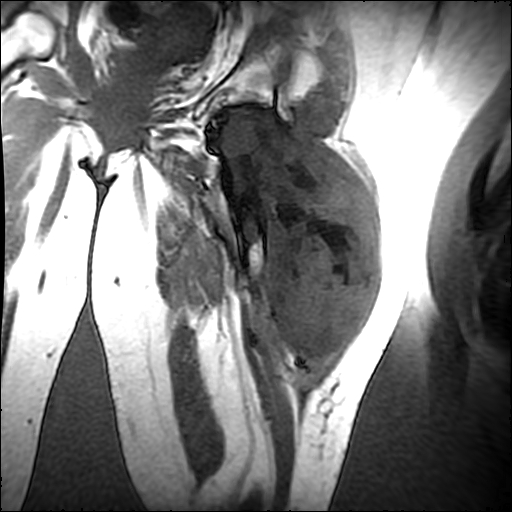

左侧大腿外伤10余年,当时情况不清,发现左侧大腿肿胀7年余,而后又有多次外伤史,近1年来出现疼痛,减重半年。查体:左侧大腿肿胀明显,皮温、肤色正常。

增强

软组织肿块,股骨破坏,增强不均匀强化-----支持恶性肿瘤